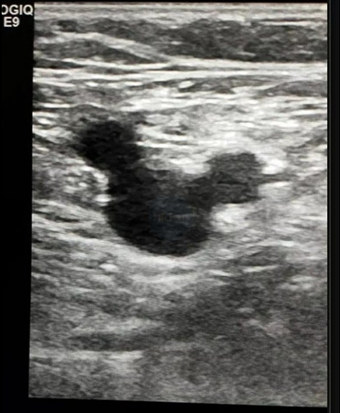

その雑誌にはX線写真やエコー像でマニアックな名前がついているものがコラムとして毎号連載されていたんです。今でも覚えているのが「ミッキーマウスサイン」ってやつで、肝臓のエコーで脈管が3つ、門脈と総胆管と肝静脈がちょうどミッキーマウスの顔と耳のように並んでいることから名付けられたようです。これも商品名といえるでしょうか。

ところがこれ、大腿部のエコーでも同じ名前の画像所見があるようです。こちらは図5のような感じで、総大腿動脈(common femoral artery)、総大腿静脈(common femoral vein)と大伏在静脈(great saphenous vein)の3つ、と書かれていますね。ディズニーさんは著作権にたいへん厳しくて、マルを3つ重ねてそれらしくなってしまっただけでも「アウト!」っていうような都市伝説を聞いたことがあるんですが、この画像、大丈夫でしょうか。自然現象(?)ですもんね、いけますよね。